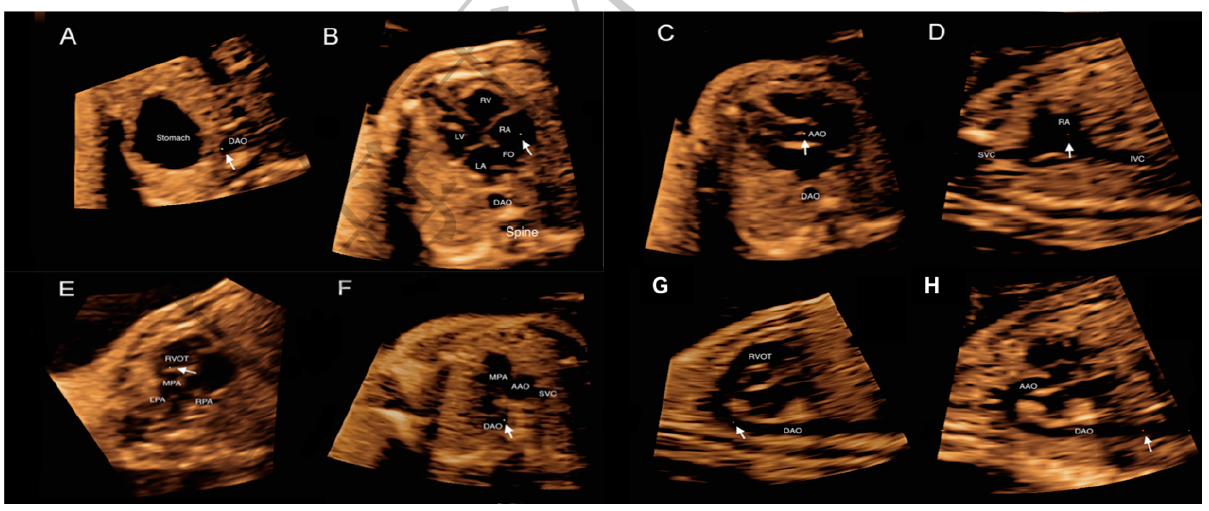

时空关联成像技术(STIC)后处理获得心脏切面图像

孙锟将攻克这一难题视为己任,开启长达5年的“摸黑生活”。摸黑,指的是超声,为了不影响诊断,超声室必须长年拉着窗帘。“有时候真的不知道白天黑夜。”他提出了用超声切五个剖面即可诊断复杂先心病的结论,俗称五剖切面。这一诊断方法成果填补了国际空白,使先心病的术前诊断获得突破性进展,对降低婴幼儿心脏手术死亡率有着重大意义。

2007年起 ,团队在三维超声的基础上,国际上首创开发了心脏虚拟内窥镜技术,成功建立多模态图像心脏虚拟内窥镜系统平台,对圆锥动脉干畸形等复杂先心病的诊断准确率明显高于心血管CT,且显著缩短了诊断时间。